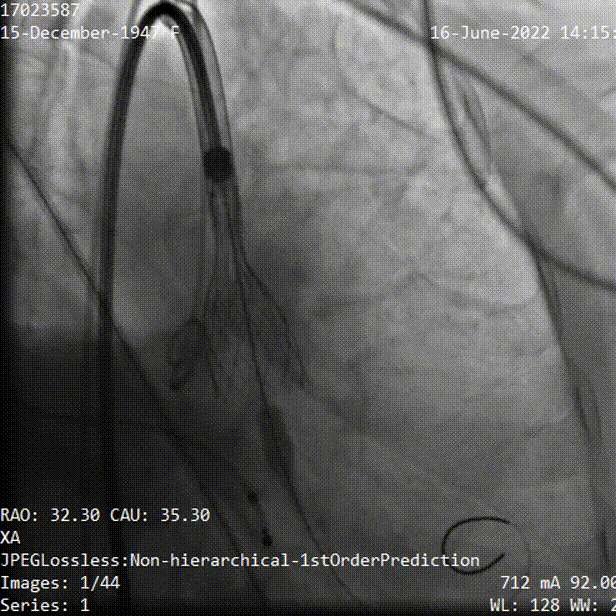

手术过程

主动脉根部造影,主动脉瓣开放受限,中度反流,采用20mm球囊预扩,有明显腰征,无造影剂渗漏,测压差70mmHg左右。

主动脉根部造影

球囊预扩